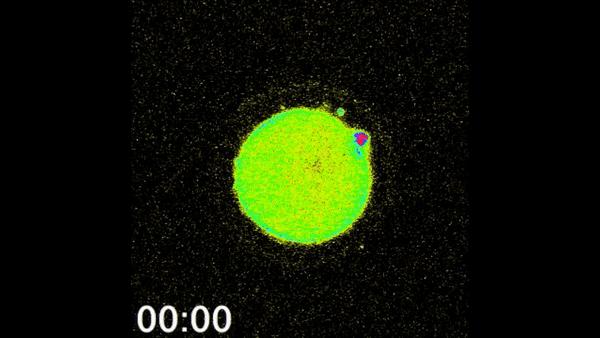

有不少人感到很困惑,这种闪光怎么被拍摄到的,你不会想到是把摄像头伸到体内里面去拍吧!其实从技术上来说,这个问题并不难解决,借助X射线荧光显微镜和电子显微镜,研究人员在卵细胞受精过程的培养基上就可以拍到这种闪光了。

卵细胞受精时的惊人闪光/美国西北大学

还有一点要值得大家注意,研究人员发现,受精胚胎的质量跟锌烟花的程度有关系。锌烟花越灿烂,受精胚胎的质量也就越高。因此,想孕育下一代的读者们,特别是女读者们要注意了,从现在开始,好好储备锌吧!